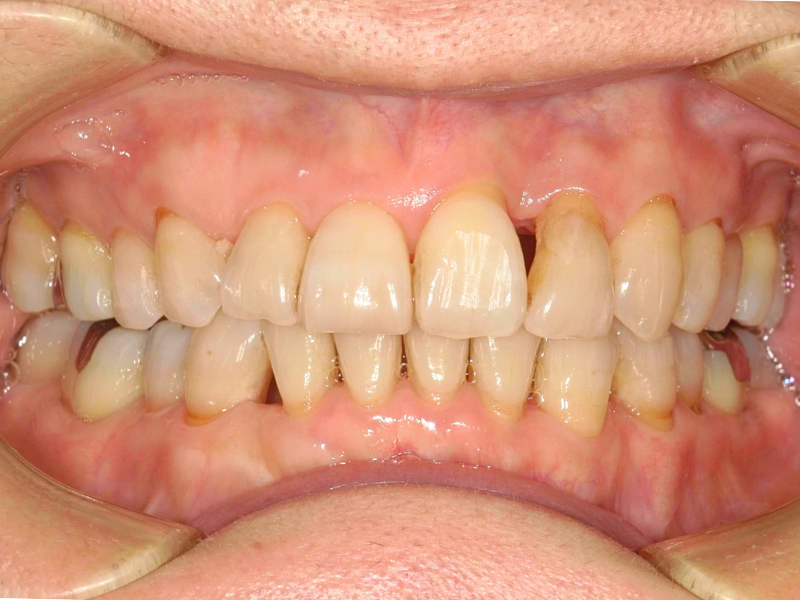

10代、女性、ワイヤー

| 施術内容 | 主訴:上下前歯でこぼこ。なるべく抜きたくない。 詳細:ワイヤー矯正での歯並び改善 詳細:ワイヤー矯正での歯並び改善 歯肉炎リスクあるため、今後は後戻りのチェックとともに歯肉炎管理もしていきます。 |

| 治療期間 | 12ヶ月(2/6現在 治療終了) |

| リスク・副作用 | ■リスク・副作用 ・治療の初期段階では、痛みや不快感が生じやすくなりますが、一週間前後で慣れます。 ・歯の動き方には個人差があるため、予想された治療期間より延長する場合があります。 |

| 費用 | ワイヤー矯正 60万円(税込660,000円) |